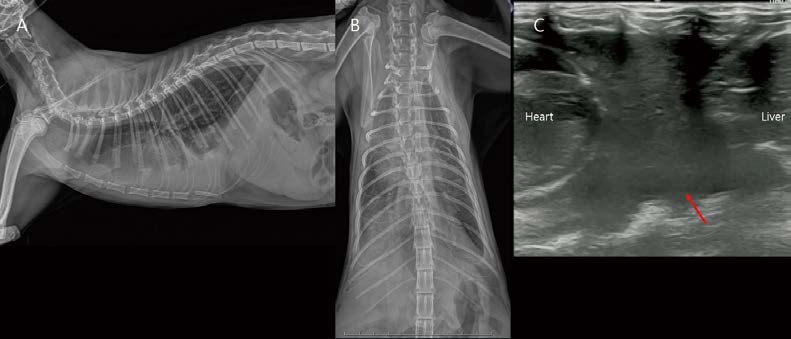

[대한수의사회지 24.png

11살, 중성화 수컷, 5.1kg, Persian cat이 호흡곤란으로 내원했습니다. 흉부 방사선 검사에서 다량의 흉수가 관찰됩니다. 모든 폐엽은 round contour를 보입니다(A, B). 흉수 천자 시 감염 없는 유미흉으로 확인되었습니다. 유미흉의 원인을 알기 위해 추가 검사(e.g., CT lymphangiography and angiography)가 필요하나, 보호자님은 일시적인 초음파 가이드 흉수 천자만을 원하셨습니다. 흉수 천자 이후 환자는 호흡이 일시적으로 개선되었습니다(C, D). 그러나, 흉수량은 점점 더 증가하고 폐엽은 더 irregular하게 둥글게 collapse되어 관찰됩니다(E, F). 이번 흉수 천자는 기흉 발생 위험이 충분히 고려되는 상황이었으나, 보호자님의 요청에 의해 진행하였고, 흉수 천자 시작한지 얼마되지 않아, 환자는 기흉 발생으로 호흡 곤란이 더 심해졌습니다(G, H, 붉은 화살표). 이제 흉수와 기흉(spontaneous pneumothorax)이 혼재되어 호흡 곤란의 임상 증상이 조절되지 않는 상태가 되었고(G, H), 일주일 이내 사망하였습니다.

다음 환자도 idiopathic chylothorax(A, CT lymphangiography)로 진단된 고양이입니다. 안정적인 마취를 위해 흉수 천자를 소량 진행하고 촬영한 흉부 방사선 검사에서 소량의 기흉이 고려됩니다(C, E). CT 검사에서 폐엽 말단 부위에서 small parenchymal consolidation 영역 및 visceral pleural thickening이 관찰됩니다(노란 화살표). 이 주변으로 소량 기흉이 관찰됩니다(붉은 화살표). Idiopathic chylothorax + Fibrosing pleuritis + Spontaneous pneumothorax 상태라 할 수 있겠습니다. 보호자님이 Idiopathic chylothorax 수술적 교정은 원치 않으셨고, spontaneous pneumothorax 정도가 미약하여, 의뢰 병원에서 어느 정도 관리 중이라고 하였습니다. 고양이 흉수에서 폐엽의 irregular 정도, round contour 정도 평가는 환자의 예후에 매우 중요한 정보이며, 흉부 방사선에서도 어느 정도 평가가 가능하므로, 세밀한 판독이 추천됩니다.